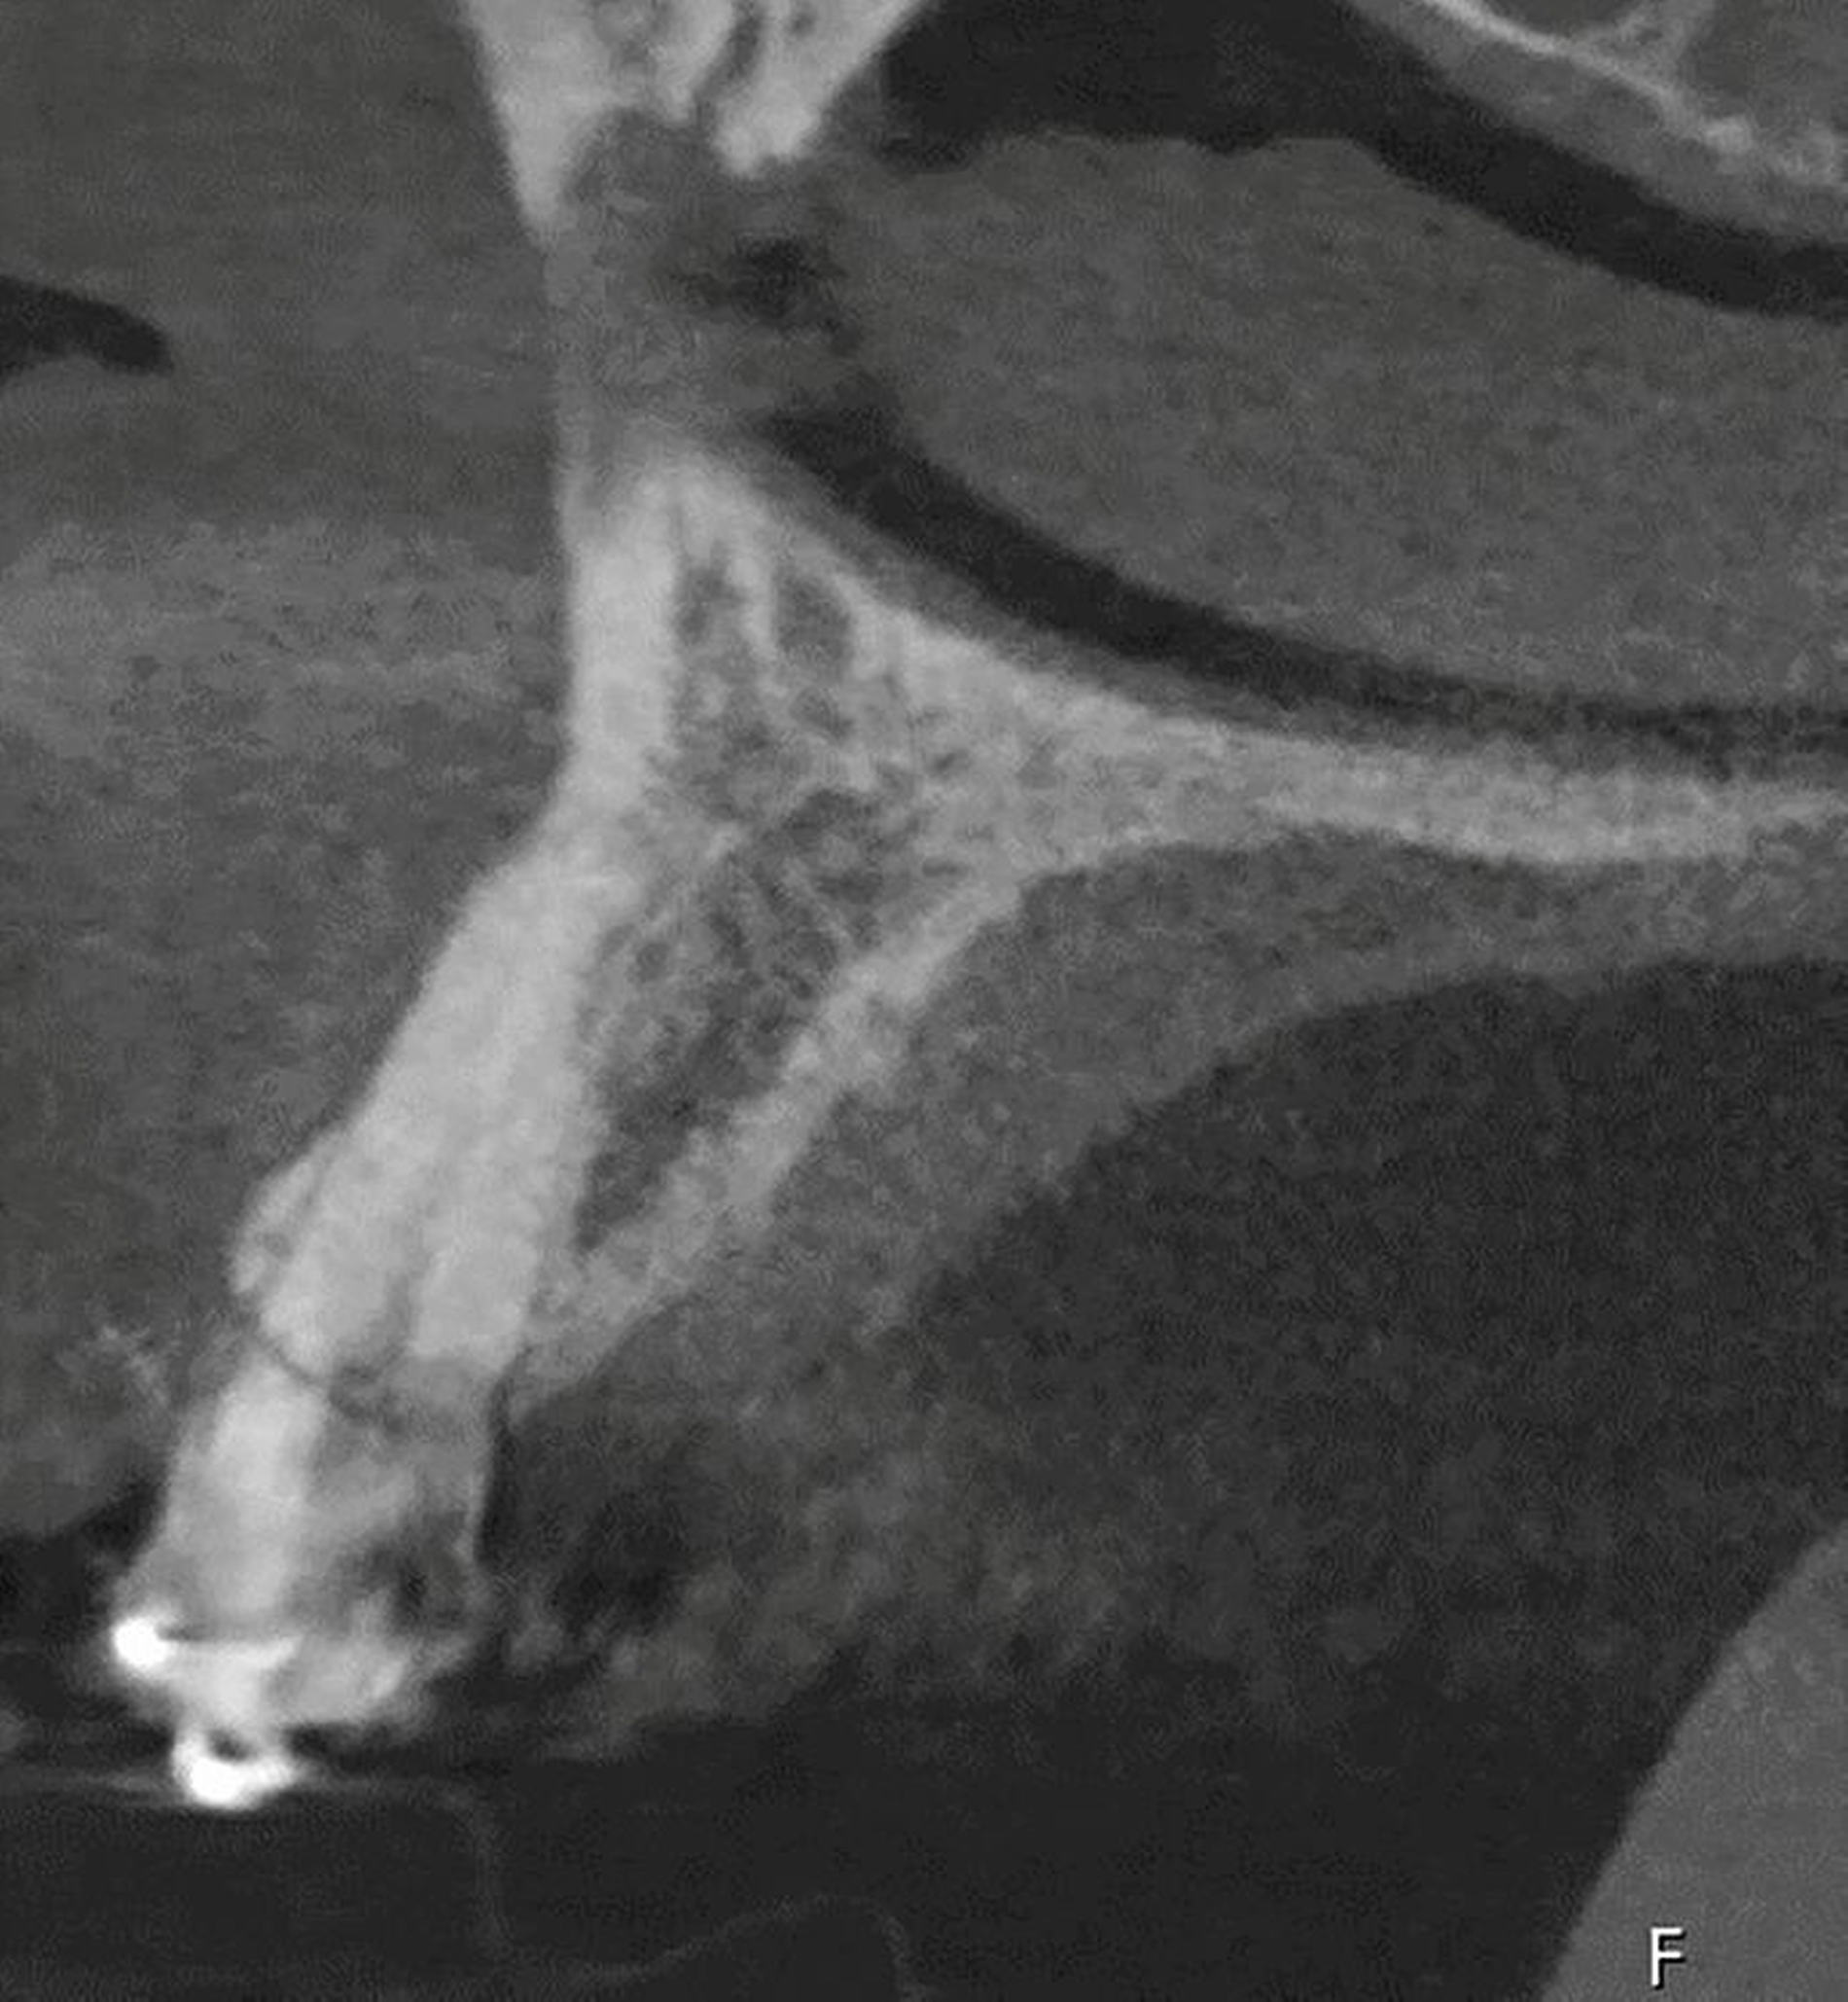

Anhand der von uns durchgeführten Einzelzahnaufnahme konnte die alio loco gestellte Erstdiagnose korrigiert werden: Wurzelfraktur des Zahnes 22 mit Kommunikation zur Mundhöhle (Abbildung 19). Der Patient favorisierte nach Diagnosesicherung zunächst Zahnersatz an 22 durch ein Sofortimplantat, weshalb eine DVT-Aufnahme zur weiteren Planung angefertigt wurde (Abbildung 20). In der Aufnahme zeigte sich jedoch, dass keine suffiziente vestibuläre Knochenlamelle vorhanden und somit der Erfolg eines Sofortimplantats nicht sicher vorhersagbar war. Nach umfassender Aufklärung entschied sich der Patient für den Zahnerhalt und eine Extrusion mit Magneten (Abbildungen 21 bis 24).